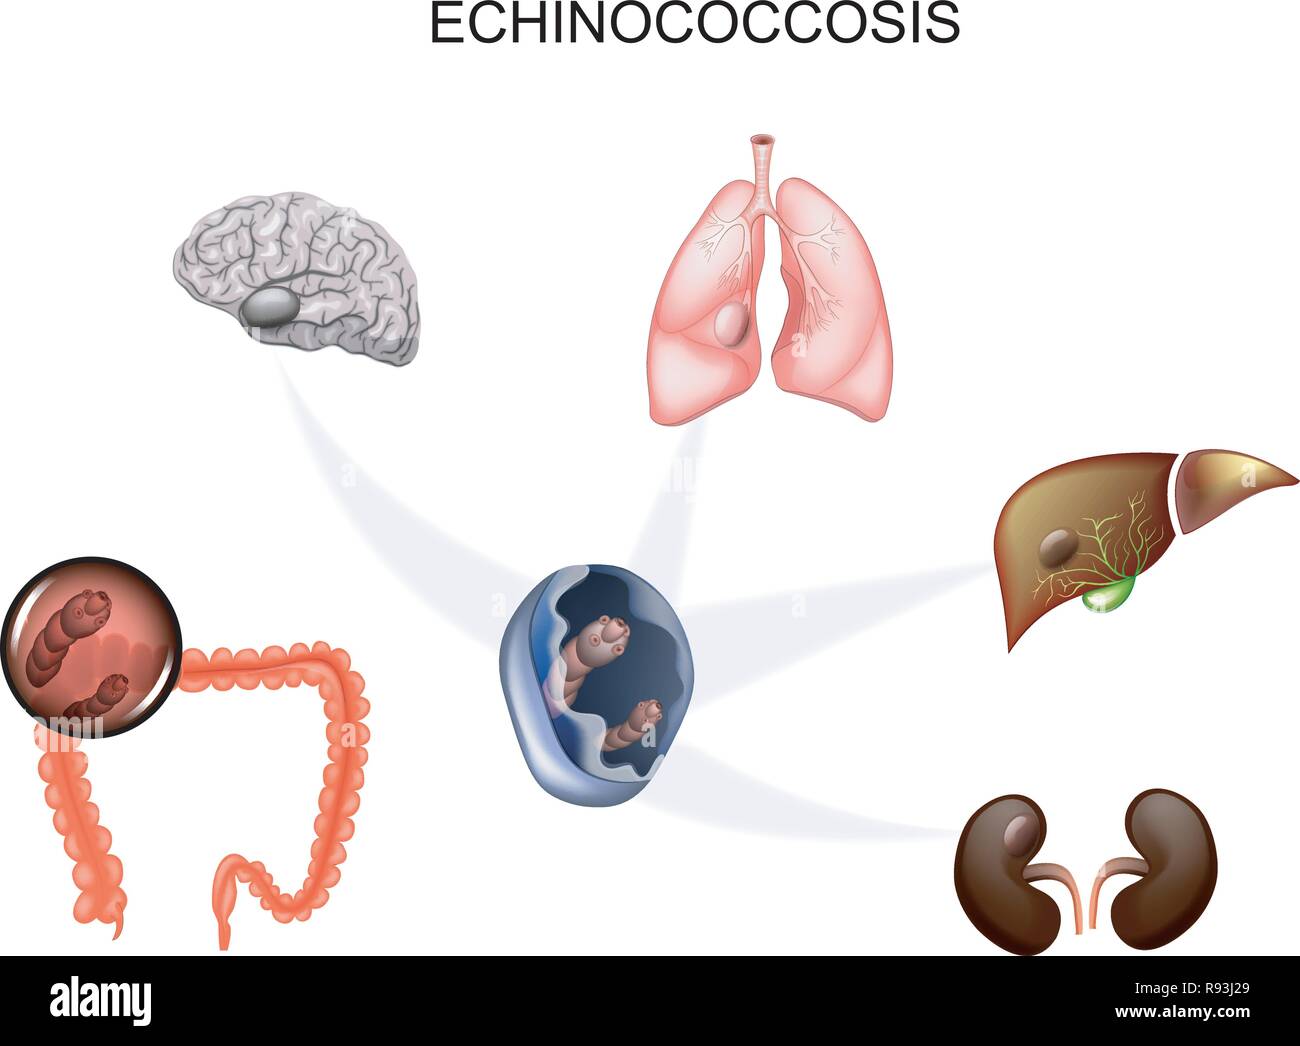

vector illustration of hydatid cyst of the brain, liver, lungs and kidneys. the causative agent Echinococcus Stock Vectorhttps://www.alamy.com/image-license-details/?v=1https://www.alamy.com/vector-illustration-of-hydatid-cyst-of-the-brain-liver-lungs-and-kidneys-the-causative-agent-echinococcus-image229346721.html

vector illustration of hydatid cyst of the brain, liver, lungs and kidneys. the causative agent Echinococcus Stock Vectorhttps://www.alamy.com/image-license-details/?v=1https://www.alamy.com/vector-illustration-of-hydatid-cyst-of-the-brain-liver-lungs-and-kidneys-the-causative-agent-echinococcus-image229346721.htmlRFR93J29–vector illustration of hydatid cyst of the brain, liver, lungs and kidneys. the causative agent Echinococcus